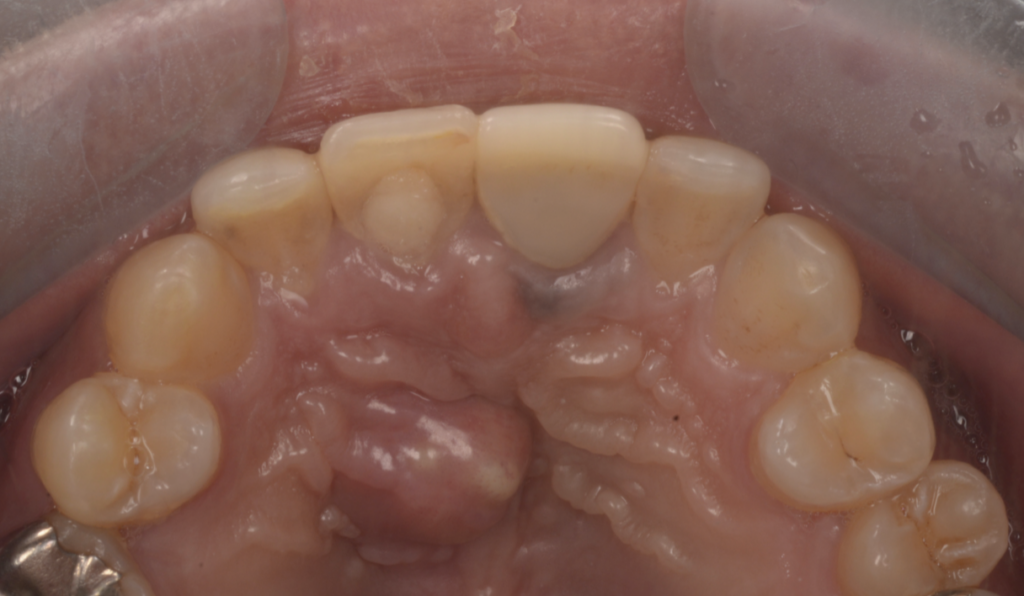

診断の鍵はCT(CBCT)|「2つの病変」を見極めて治療戦略を分ける

前歯部の病変は平面レントゲンだけでは重なりが生じやすく、

「根尖性病変なのか」「嚢胞が主体なのか」「併発なのか」が分かりにくいことがあります。

当院ではCT(CBCT)を用い、

- 根尖部の感染(根尖性歯周炎)

- 切歯管周囲の嚢胞性病変(切歯管嚢胞)の関係を立体的に評価し、原因に合わせて治療を組み立てます。

術後経過|3ヶ月で骨ができてきている所見を確認

術後3ヶ月の時点で、画像上、骨形成(骨ができてきている)ことを確認しています。